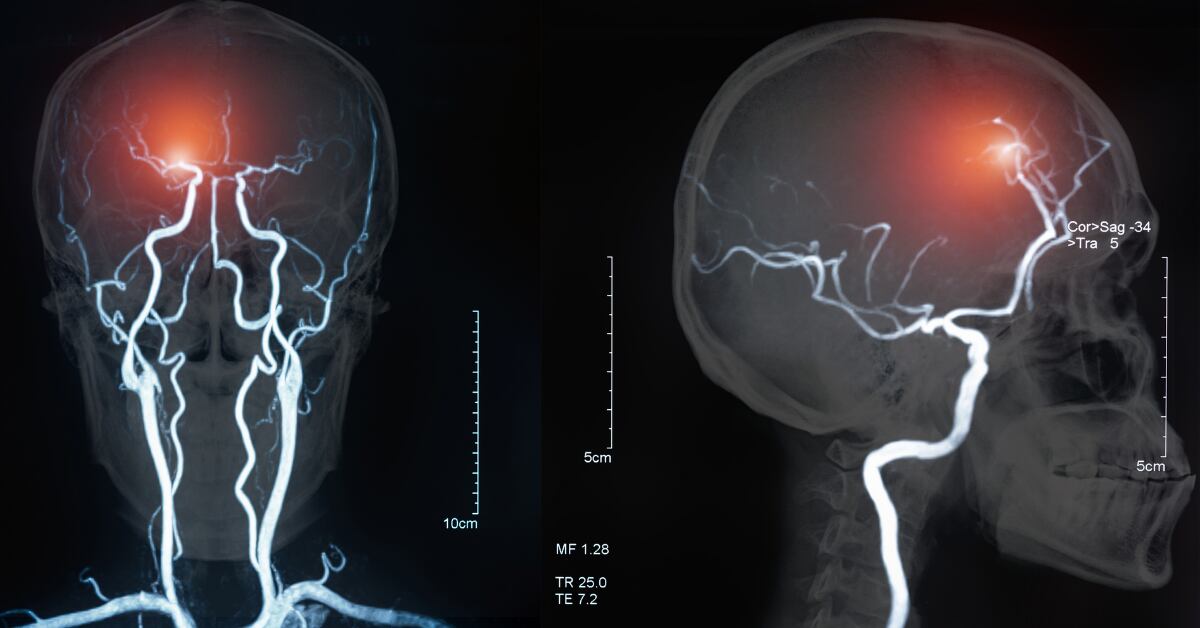

Explicamos a continuación qué son estos microinfartos del cerebro.

Microinfartos cerebrales: qué son

Un microinfarto cerebral es un infarto cerebral pequeño. Con síntomas que duran menos tiempo y con afectaciones que no se traducen necesariamente en una discapacidad notoria. Ambos, un microinfarto o un infarto más severo, son eventos cerebrovasculares. Estos pueden ser llamados por varios nombres que seguramente has leído y escuchado numerosas veces:

Un accidente cerebrovascular (ACV) ocurre cuando la sangre deja de llegar al cerebro. Cuando se detiene el flujo sanguíneo a una parte del cerebro.

La gran mayoría de las veces (un 80% de los casos), los ACV son isquémicos, es decir, causados por un coágulo de sangre que bloquea o tapa un vaso sanguíneo en el cerebro (vaso = tubo a través del cual la sangre circula por el cuerpo). El 20% restante los ACV son hemorrágicos; causados por un vaso sanguíneo que se rompe y sangra en el cerebro.

“Generalmente estos son infartos que ocurren en la sustancia blanca del cerebro, por daño en las pequeñas arterias penetrantes del cerebro, que son muy susceptibles al daño por hipertensión, diabetes, fumado, colesterol alto, uso de drogas, o incluso por el envejecimiento, entre otras causas. En la gran mayoría de los casos se presentan en pacientes que tienen estas condiciones. Recordemos que más de un millón de costarricenses son hipertensos. El problema es que muchos de estos infartos son silentes, o sea que aparecen sin dar síntomas. La persona se entera que los tiene por que se hace una resonancia magnética, en ocasiones por otros temas, la mayoría no son visibles en el TAC (tomografía axial computarizada)”.